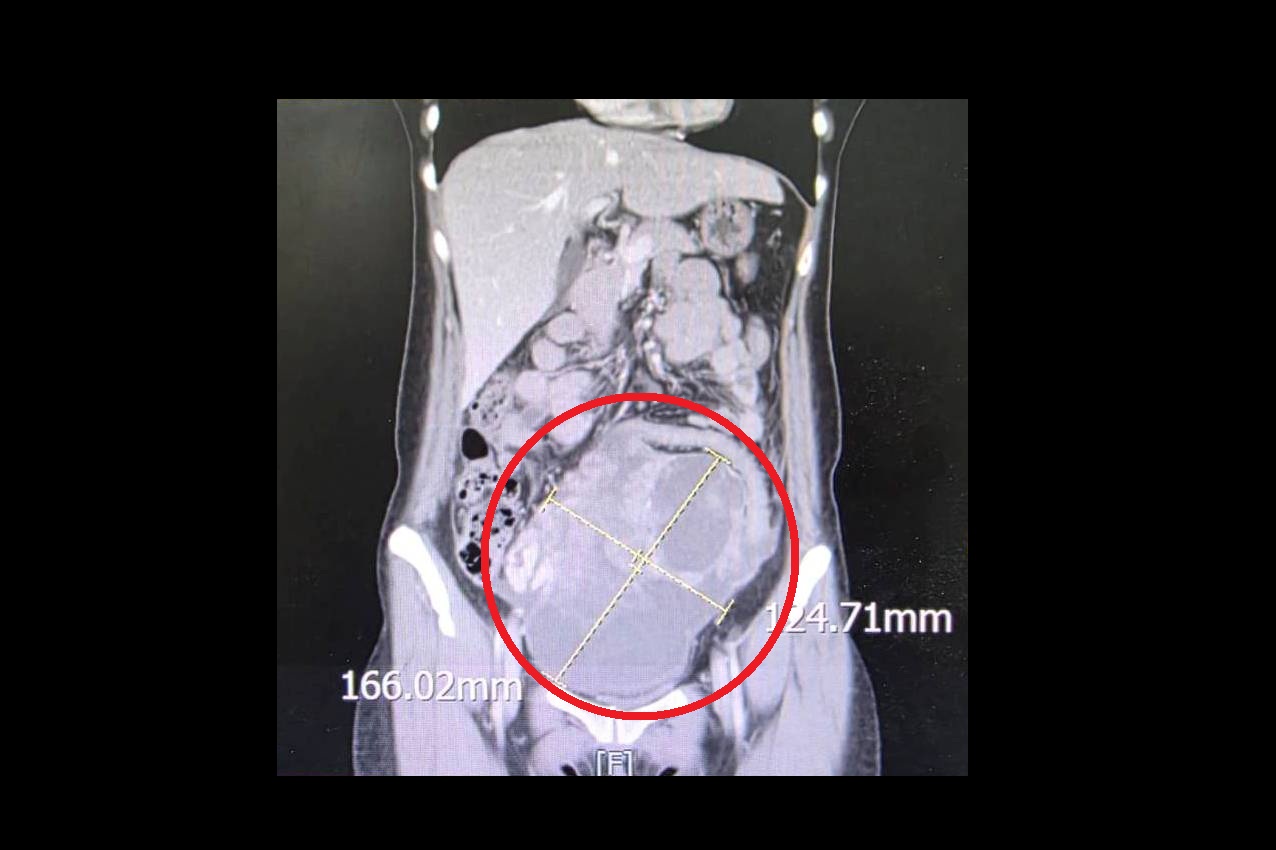

病人就醫發現腹部直徑高達16公分的巨大腫瘤紅圈處,病理報告為罕見的同步性子宮內膜(圖/大千醫院提供)

【特派員黃義雄/苗栗報導】 一名44歲未婚女性,持續兩週感到腹痛、腹脹且食慾不振,原以為是腸胃不適,就醫檢查後竟在腹部發現直徑高達 16公分的巨大腫瘤,且癌症指數(CA-125)飆升至 900 U/ml(正常值為 <35 U/ml)。大千綜合醫院婦產科劉榮啟醫師緊急安排手術切除子宮及兩側卵巢,術後病理報告證實為罕見的「同步性子宮內膜癌與卵巢癌(SEOC)」。在醫療團隊悉心治療下,病人至今已成功抗癌滿5年,復原狀況良好。